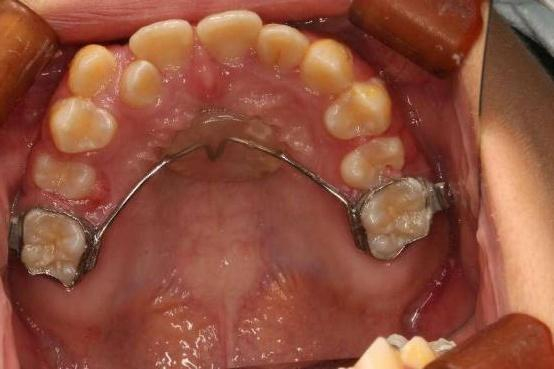

对于牙弓比较窄小而引起的拥挤,经过X光片的检查和模型的分析,可以通过扩弓来增加空间,从而不拔牙排齐牙齿。